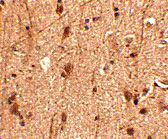

Immunohistochemistry of Slitrk3 in human brain tissue with Slitrk3 antibody at 2.5 μg/mL